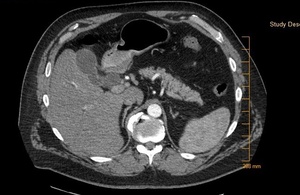

His laboratory values were significant for elevated total and direct bilirubin (22.4 and 15.9 mg/dl). Additional lab values include – an AST (137 U/L) and ALT (232 U/L), and an abnormally elevated Lipid panel with LDL (263 mg/dl), triglyceride (357 mg/dl), and total cholesterol (346 mg/dl). On day three of admission, the patient underwent an endoscopic retrograde cholangiopancreatography (ERCP) with findings significant for multiple gallstones in the common bile duct (Fig. 1 - 4) consistent with Mirizzi syndrome.

On the ERCP, patient had outpouching in the cystic duct. A stent was placed in the common bile duct (CBD). The patient’s direct bilirubin decreased from 7.4 mg/dl to 5.9 mg/dl. The patient was scheduled to follow up with gastroenterologist in two to three weeks for the removal of the CBD stent, and he improved markedly post-stent placement. He was asymptomatic on discharge.